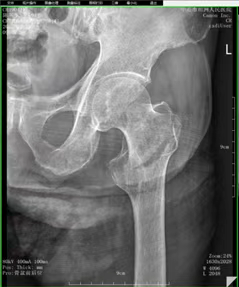

术前DR

回南天是南方地区特有的气候现象,近期我院收治十几名因回南天地面湿滑摔伤的患者,94岁的陈爷爷因摔伤致左髋关节疼痛不能活动来我院骨科入院治疗。医生诊断其为左股骨粗隆间骨折。